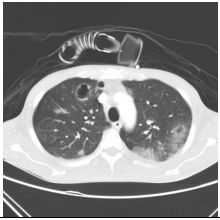

4. 39 y/o female, productive cough for 2 months